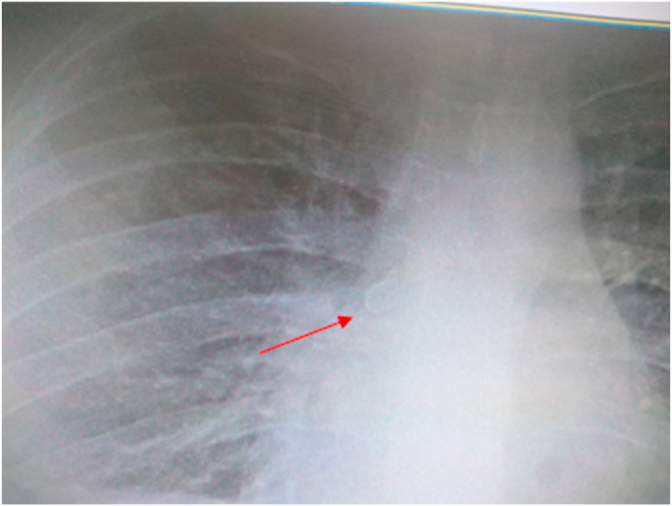

After 5 days, the patient's general condition improved and he was discharged to his own personal satisfaction. However, he was referred to our hospital 24 hours later due to the persistence of his cough and SOB. He was admitted under the supervision of a pulmonologist, and HRCT and RT-PCR were ordered. The result of the lung HRCT showed mosaic attenuation in the right middle and lower lobes due to air trapping (Fig. 1). In addition, the RT-PCR for COVID-19 was negative. Moreover, the results of the chest X-ray (CXR) revealed a round opacity in the right main bronchus (Fig. 2). Clinical suspicion was placed on the FBA based on the radiologist's comment (Fig. 1, Fig. 2). Rigid bronchoscopy was performed to further investigate and diagnose the patient, and an olive kernel was discovered in the right main bronchus (Fig. 3 A, B).

Fig. 2.

A round opacity showing in the right main bronchus (arrow head) on chest X-ray.